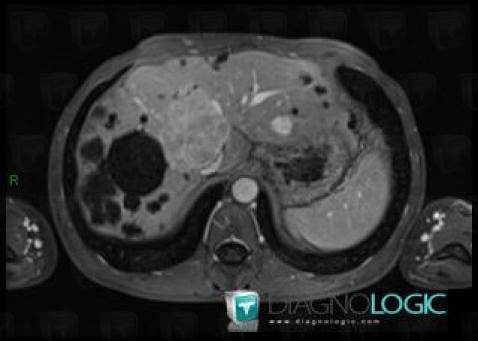

Polykystose rénale, Foie, IRM

Voici les informations spécifiques à l'image clé ci dessus:

- Diagnostic Polykystose rénale, Localisation(s) Foie, comportant les gammes Lésion hépatique en hypersignal T2

- Diagnostic Polykystose rénale (lié à Polykystose hépatique), Localisation(s) Foie, comportant les gammes Lésion hépatique kystique

Hyperplasie nodulaire focale, Foie, IRM

- Diagnostic Hyperplasie nodulaire focale, Localisation(s) Foie, comportant les gammes Lésion hépatique en hypersignal T2